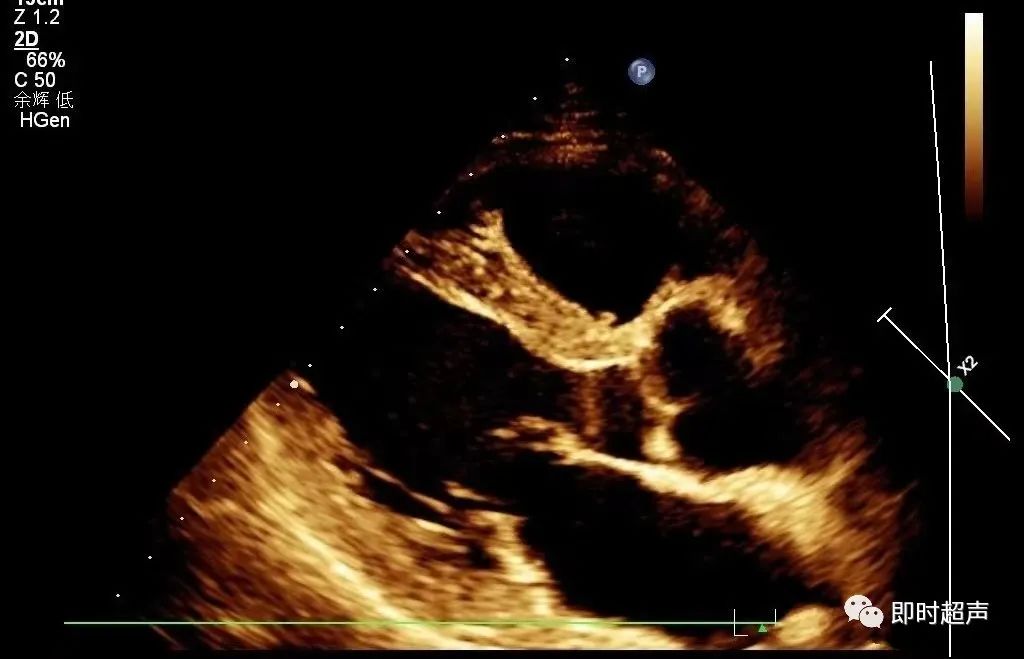

★室间隔及左室后壁厚度

测量切面:胸骨旁左室长轴切面;测量位置:二尖瓣腱索水平,分别测量舒张末期及收缩末期室间隔及左室后壁的厚度。